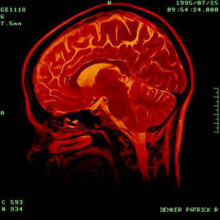

Brain Cancer Risks of Mobile Phones for Real

Science has confirmed that the trusty mobile gadget - which now comes as a smartphone or feature phone - emits radiation, ramping up fears that humans may indeed develop brain cancer from excessive use of the ubiquitous device.

In May 2011, the World Health Organisation (WHO) listed cell phones as likely contributors to brain cancer, specifically glioma and acoustic neuroma brain conditions.